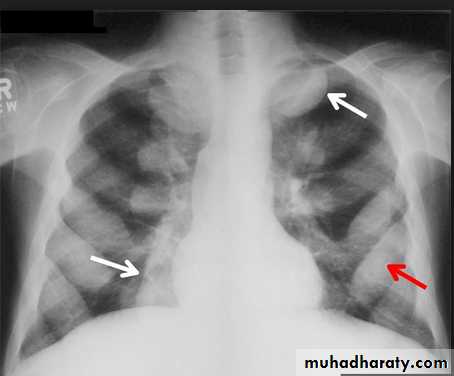

Tension pneumothorax.

On a posteroanterior chest x-ray (A), the left hemithorax is very dark or lucent because the left lung has collapsed completely (white arrows).

The tension pneumothorax can be identified because the mediastinal contents, including the heart, are shifted toward the right, and the left hemidiaphragm is flattened and depressed. A computed tomography scan done on a different patient with a tension pneumothorax (B) shows a completely collapsed right lung (arrows) and shift of the mediastinal contents to the left.